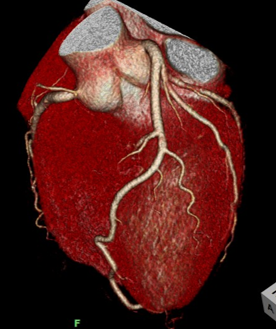

当クリニックでは、クリニックとしては珍しく、造影検査も行っています。主に心臓(冠動脈)や大動脈などの血管の検査が多い傾向です。様々な検査目的を満たすために、撮影方法や造影剤注入法、画像処理などを工夫し、より良い画像を提供しています。